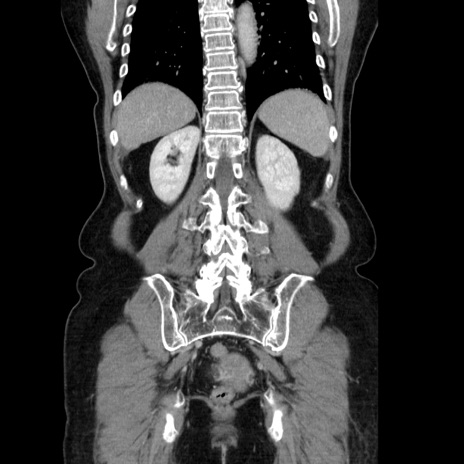

症例5(冠状断像)

【症例】70歳代女性

【主訴】お腹が張る

【現病歴】1週間くらい前から腹部膨満の自覚あり。昨日夜から増悪したため、本日救急外来受診。

【身体所見】意識清明、BT 36.5℃、BP 165/106mmHg、HR 80bpm、SpO2 98%、腹部:膨満、軟、自発痛・圧痛なし、触診にて不快感あり、腸蠕動音:減弱

【データ】WBC 12600、CRP 1.04